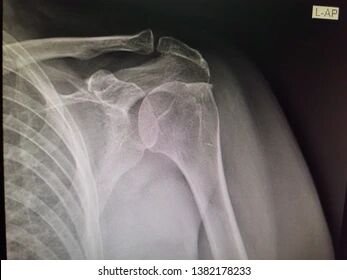

錯誤(A) 盂肱關節前向脫位(anterior dislocation)

glenoid與肱骨頭,仍有重疊,無empty